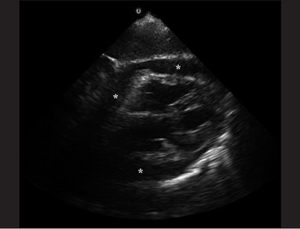

Ultrasound

- Pericardial effusion

- In acute cases, even a relatively small build up of pericardial fluid can lead to hemodynamic compromise

- Diastolic collapse of the right atrium (in atrial diastole)

- Diastolic collapse of the right ventricle

- Plethoric IVC